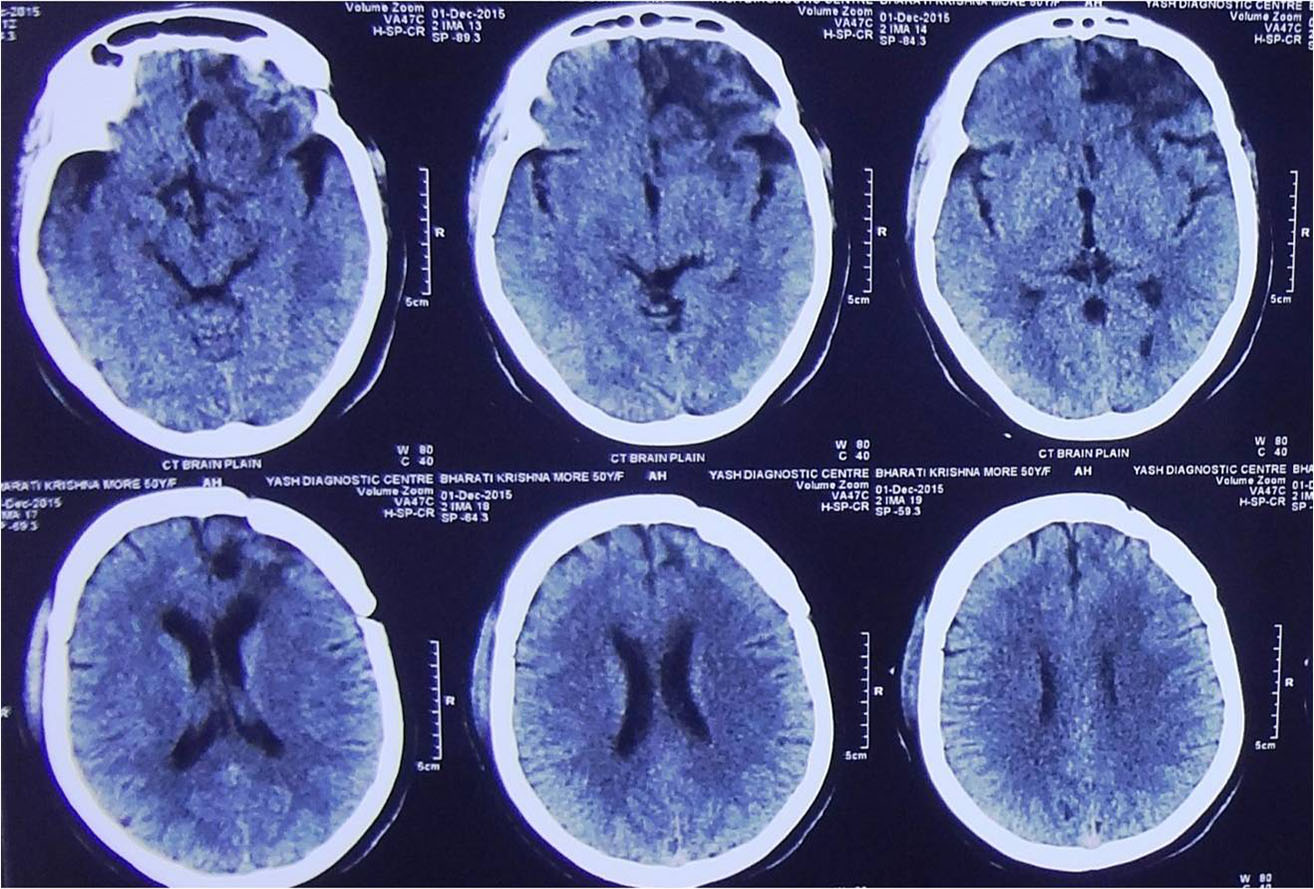

Traumatic Brain injury is defined as damage to the brain resulting from external mechanical force,

commonest causes of brain injury are vehicular accidents, assaults, and accidental falls etc.

Traumatic Brain injury is a major cause of death and disability worldwide, especially in children and young adults.

Brain injuries can be minor or major life threatening. The signs and symptoms depend on the severity of injury.

Minor injuries are usually treated with medications and constant monitoring. Moderate to severe injuries require treatment in neurosurgical ICU and may require emergency surgery.